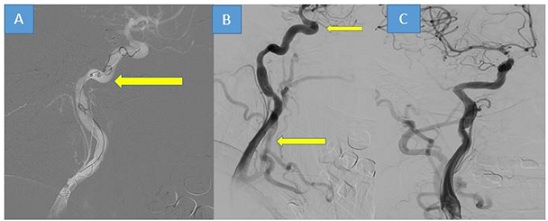

The emergency department received a 56-year-old man who had suffered multiple fractures in the skull base and facial bones, as well as a traumatic subarachnoid hemorrhage, after falling from a height of around 5 meters. Further investigation, including CTA and DSA, confirmed the presence of a direct carotid-cavernous fistula on the right side. (Figure 1).

Figure 1: Brain CT scan revealing extensive subarachnoid hemorrhage (SAH) with greater prominence on the right side. (A and B). Bone view window displaying multiple bone fractures (one of them indicated by the yellow arrow) (C). Digital Subtraction Angiography (DSA) illustrating a traumatic carotid cavernous fistula on the right side (D).